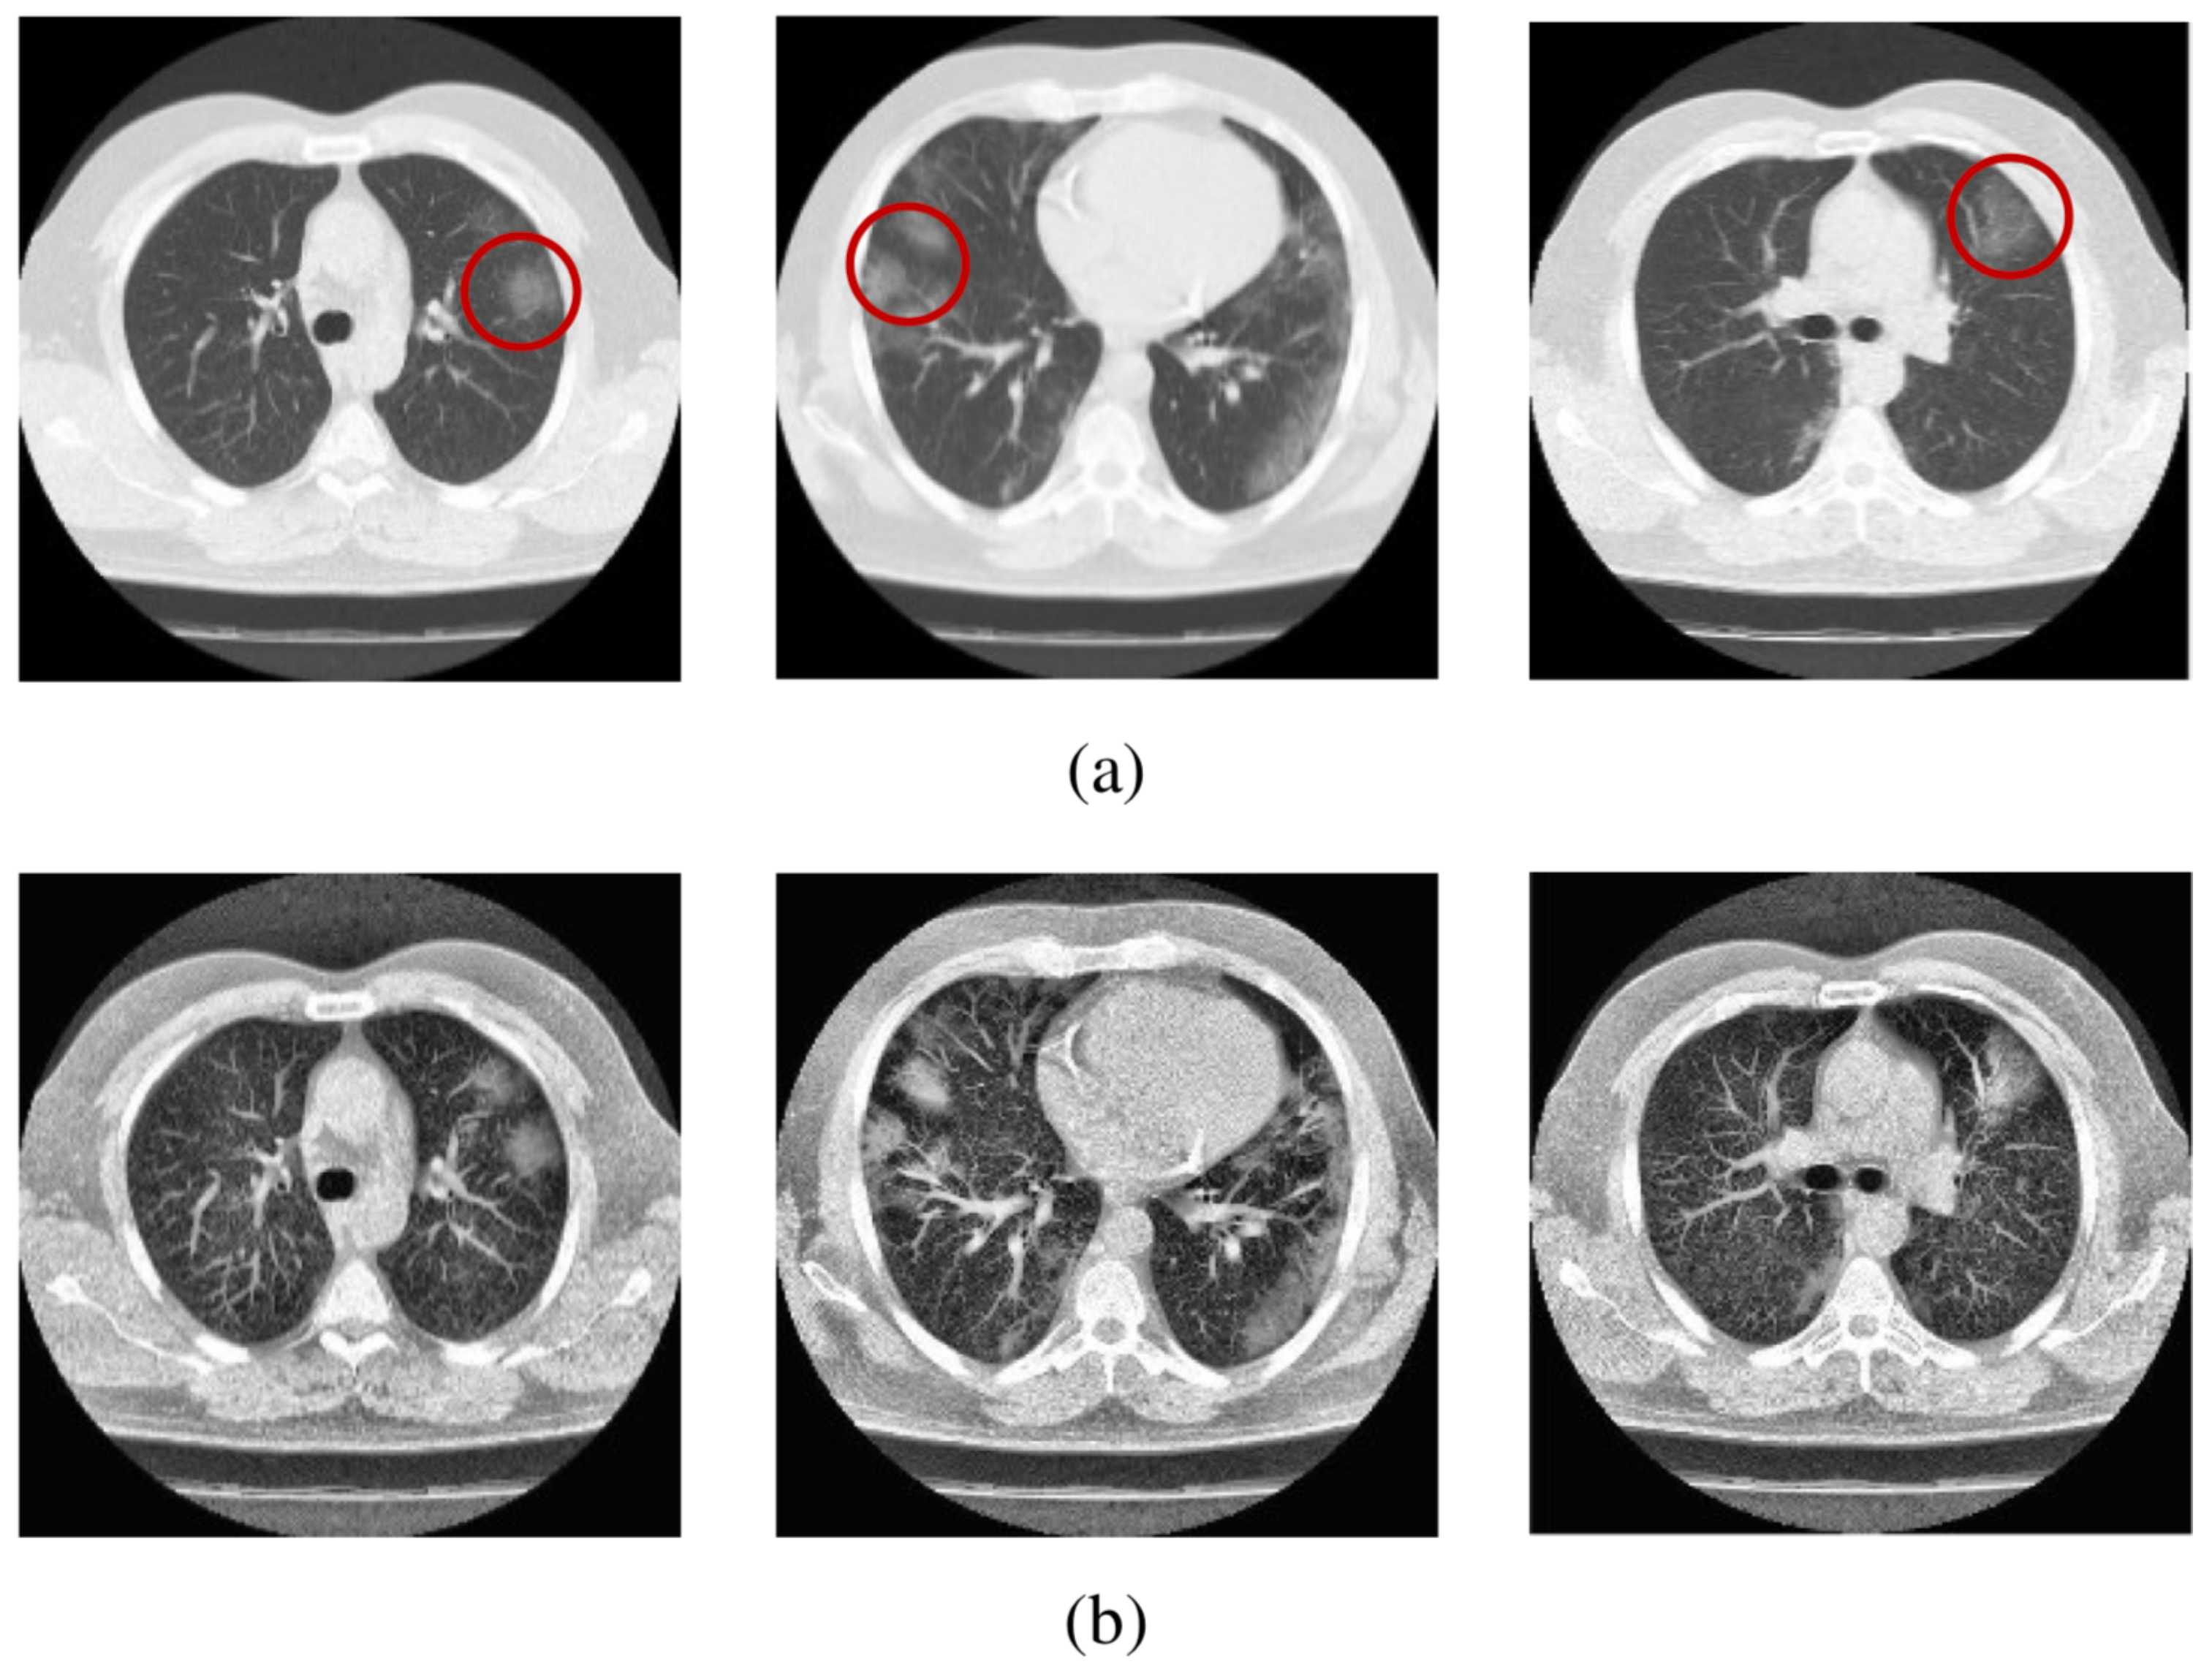

- Al-Azawi, R.J.; Al-Saidi, N.M.G.; Jalab, H.A.; Kahtan, H.; Ibrahim, R.W. Efficient classification of COVID-19 CT scans by using q-transform model for feature extraction. PeerJ. Comput. Sci. 2021, 7, e553. [Google Scholar] [CrossRef]